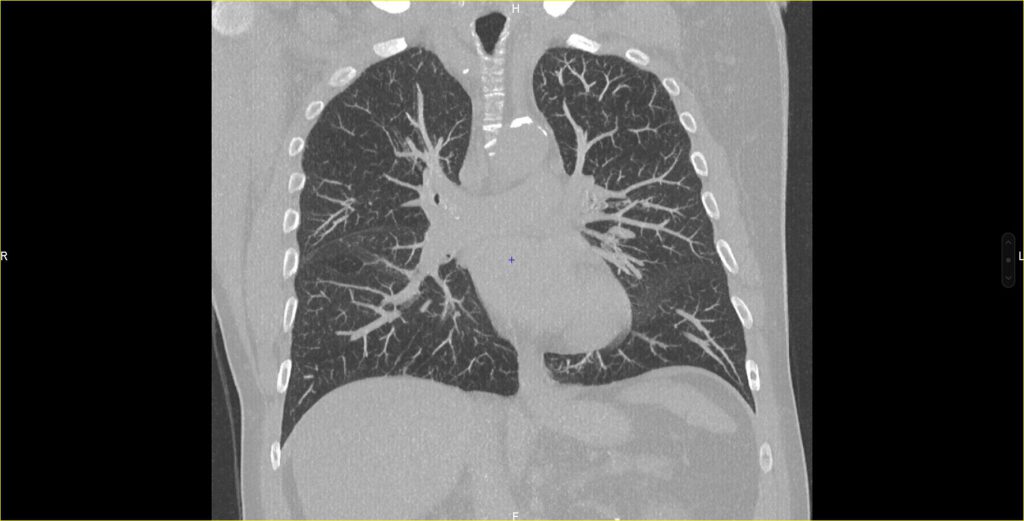

Les examens scanner : le scanner thoracique, l’angioscanner, le coroscanner...

- Scanner thoracique : L’examen de référence pour le diagnostic et le suivi des pathologies pulmonaires (pneumopathie infectieuse, cancer broncho-pulmonaire, dépistage, pneumopathie interstitielle…)